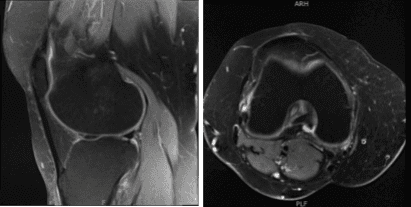

The patient presented an MRI result that showed undersurface tear of the medial meniscal body resulting in a small peripheral meniscal flap. Small radial tear at the free edge of the lateral meniscal body. Mild to moderate cartilage loss in the medial compartment and a small joint effusion.

MRI-3T Knee non-contrast